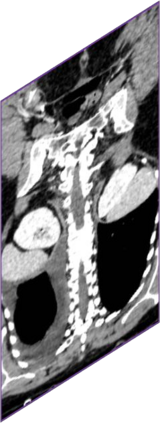

Due to the constraints of the imaging device and high cost in operation time, computer tomography (CT) scans are usually acquired with low intra-slice resolution. Improving the intra-slice resolution is beneficial to the disease diagnosis for both human experts and computer-aided systems. To this end, this paper builds a novel medical slice synthesis to increase the between-slice resolution. Considering that the ground-truth intermediate medical slices are always absent in clinical practice, we introduce the incremental cross-view mutual distillation strategy to accomplish this task in the self-supervised learning manner. Specifically, we model this problem from three different views: slice-wise interpolation from axial view and pixel-wise interpolation from coronal and sagittal views. Under this circumstance, the models learned from different views can distill valuable knowledge to guide the learning processes of each other. We can repeat this process to make the models synthesize intermediate slice data with increasing inter-slice resolution. To demonstrate the effectiveness of the proposed approach, we conduct comprehensive experiments on a large-scale CT dataset. Quantitative and qualitative comparison results show that our method outperforms state-of-the-art algorithms by clear margins.